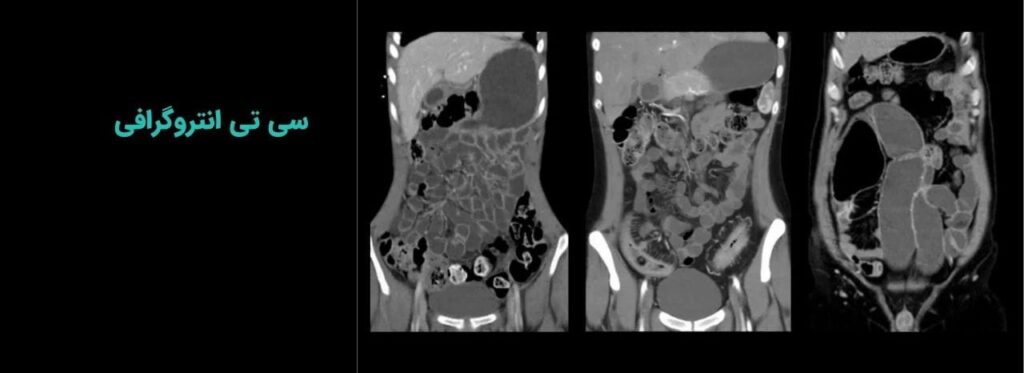

سی تی اسکن

دستگاه سی تی اسکن 64 اسلایس